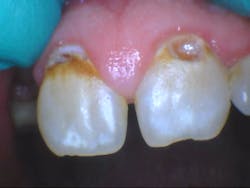

- Teeth nos. 14 and 15 both had supererupted into the 18 and 19 space (figure 2).

- Additional caries were noted on nos. 10, 11, 14, 26, 27, and 29—primarily facial/buccal caries (figures 3–8)